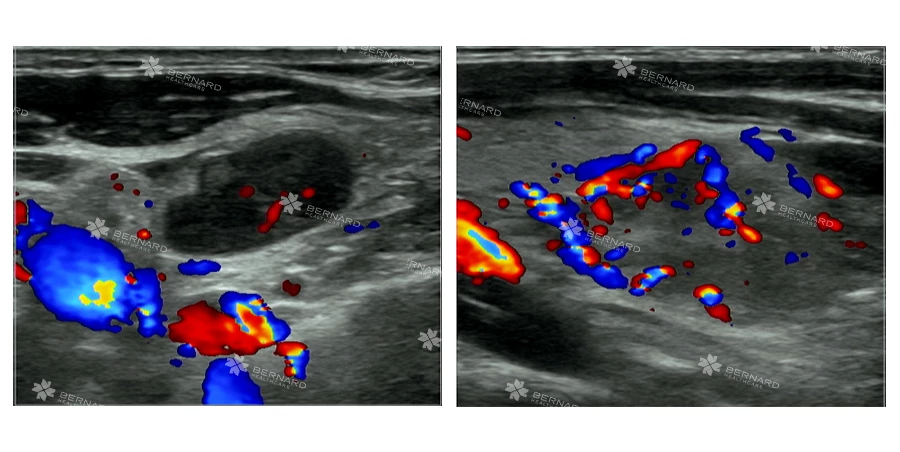

Kết quả siêu âm ghi nhận: Tại dọc cơ ức đòn chum có nhiều hạch bất thường.

Phía bên phải cổ của chị H. rải rác vài vài hạch nhóm 2,3,4 dmax#7.4x3mm, giới hạn rõ, bờ đều, còn rốn hạch, không tăng sinh mạch máu - dấu hiệu thường gặp ở hạch lành tính.

Ngược lại, dọc bó mạch cảnh và cơ ức đòn chũm phía bên trái có vài hạch echo kém, dmax# 21x8mm, giới hạn rõ, bờ đều, tăng tưới máu rốn hạch, bên trong có vùng hoại tử echo kém đồng nhất.

Thêm vào đó, siêu âm vùng nách trái cũng phát hiện một số hạch có hình ảnh không điển hình. Những dữ kiện này khiến bác sĩ Bernard nghĩ nhiều đến lao hạch nhưng không loại trừ khả năng lymphoma – một dạng ung thư hạch bạch huyết.